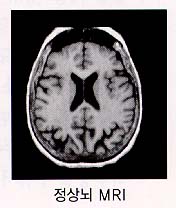

2. Ç÷°ü¼ºÄ¡¸Å

Ç÷°ü¼º Ä¡¸Å¶õ ³úÇ÷°üÁúȯ¿¡ ÀÇÇÑ ³ú¼Õ»óÀÌ ´©ÀûµÇ¾î ³ªÅ¸³ª´Â Ä¡¸Å¸¦ ¸»ÇÕ´Ï´Ù. À§ÇèÀÎÀڷδ °íÇ÷¾Ð, ´ç´¢º´, °íÁöÇ÷Áõ, ½ÉÀ庴, Èí¿¬, ºñ¸¸À» °¡Áø »ç¶÷¿¡°Ô¼

Áø´Ü

¾ËÂêÇÏÀ̸Ӻ´°ú ¸¶Âù°¡Áö·Î Ä¡¸Å¿¡ ¼÷·ÃµÈ Àǻ簡 ÁøÂû°ú ¿©·¯ °Ë»ç °úÁ¤À» ÅëÇÏ¿© Ç÷°ü¼ºÄ¡¸ÅÀÎÁö ¾Æ´Ï¸é ´Ù¸¥ ¿øÀο¡ ÀÇÇÑ Ä¡¸ÅÀÎÁö¸¦ È®ÀÎÇÏ°Ô µË´Ï´Ù. °Ë»ç¿¡´Â Ç÷¾×°Ë»ç, ´¢°Ë»ç, ÈäºÎ¹æ»ç¼±°Ë»ç, ½ÉÀüµµ ³úÆÄ°Ë»ç ¹× ÀÚ±â°ø¸í°Ë»ç(MRI) µîÀÌ ÀÖ½À´Ï´Ù. Ä¡¸Å Áõ»óÀÌ ÀÖÀ¸¸é¼ ½Å°æÇÐÀû °Ë»ç»ó ÀÌ»ó¼Ò°ßÀÌ ÀÖ°í ³ú ÃÔ¿µ»ó ±× ÀÌ»ó¼Ò°ßÀ» µÞ¹ÞħÇÒ ¼ö ÀÖ´Â ¼Ò°ßÀÌ º¸À̸é È®ÁøÇÒ ¼ö ÀÖ½À´Ï´Ù. »ó±â ¿°ÅÇÑ Ç÷°ü¼º Ä¡¸ÅÀÇ À§Çè¿ä¼Ò, ƯÈ÷ °íÇ÷¾Ð ȯÀÚ¿¡¼ ½Å°æÇÐÀû ÀÌ»ó¼Ò°ßÀÌ ÀÖ°í ±â¾ïÀå¾Ö µî »ç°í·ÂÀÇ ÀúÇϰ¡ ÀÇ½ÉµÉ ¶§´Â ÀÏ´Ü Ç÷°ü¼º Ä¡¸ÅÀÇ °¡´É¼ºÀ» »ý°¢Çϰí Ä¡¸Å Àü¹®º´¿øÀ» ¹æ¹®Çϰųª ³ú ÀÚ±â°ø¸í¿µ»óÃÔ¿µÀ» ½Ç½ÃÇÏ¿©¾ß ÇÕ´Ï´Ù.